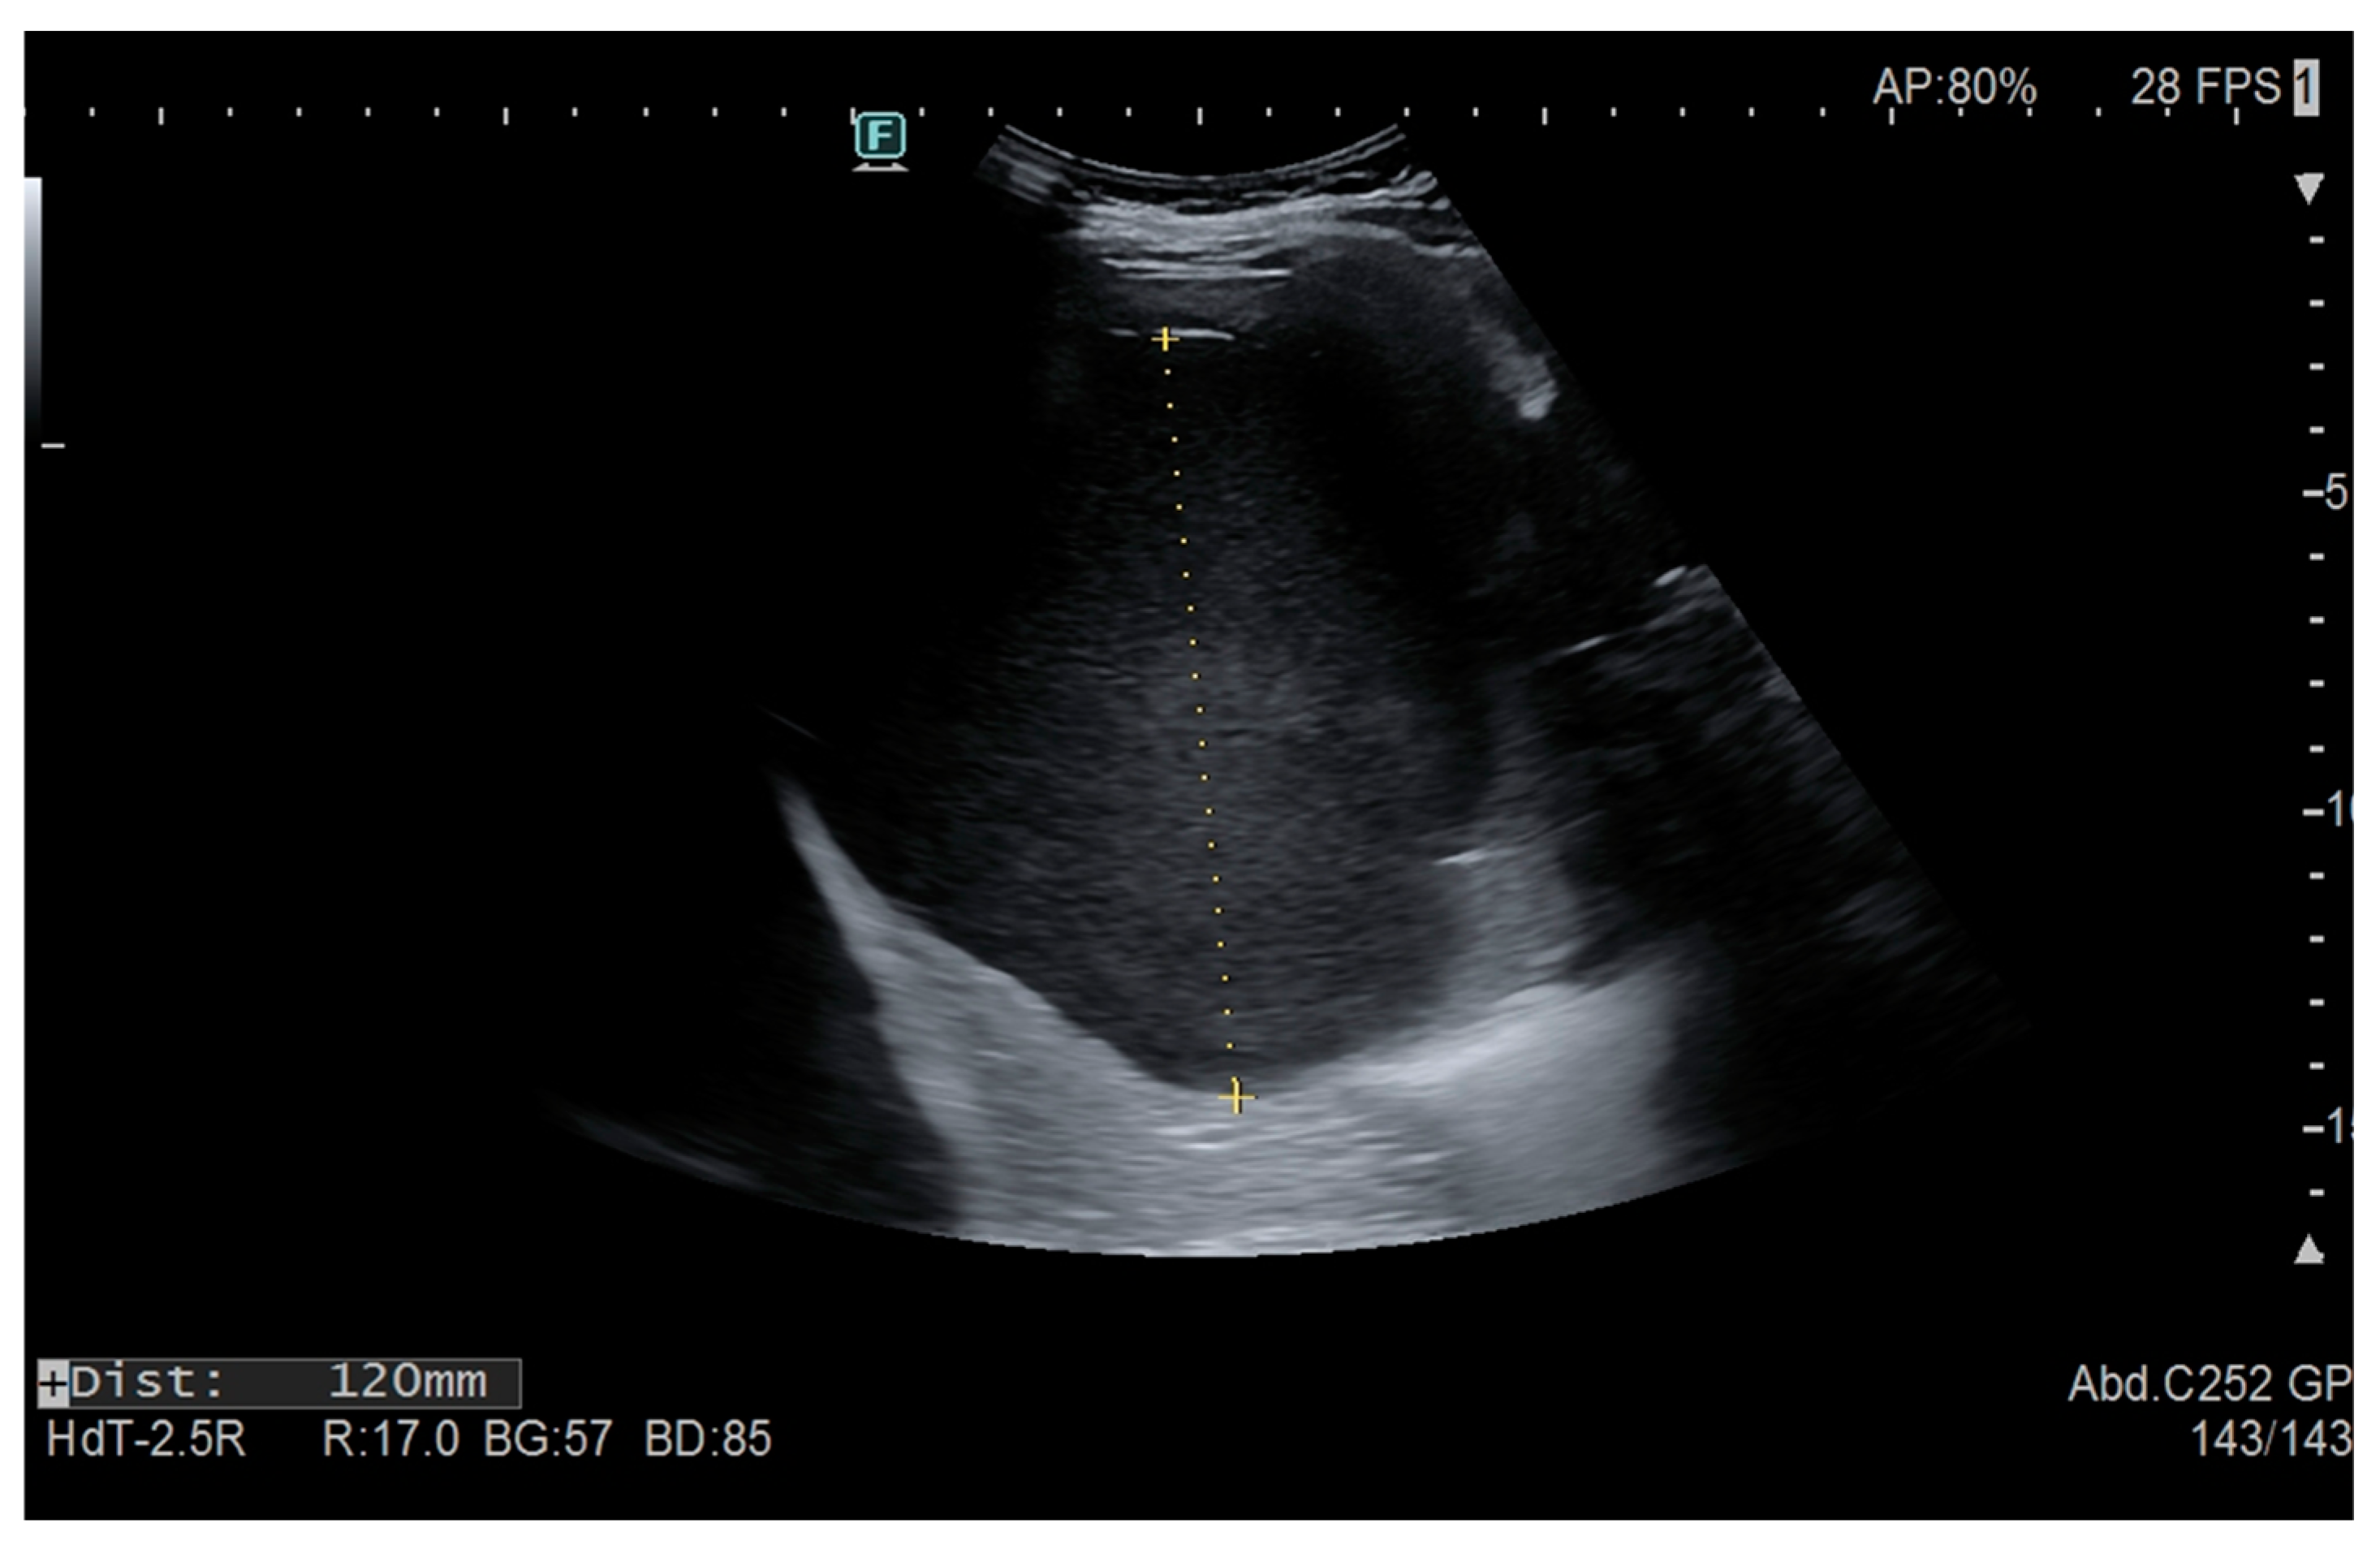

- Kofinova, D.; Rangelov, E.; Vasilevski, I.; Nansenova, V.; Bogdanova, O.; Shivachev, H. Rare case of an epidermoid spleen cyst in 15-year-old girl, XXVI National ultrasound congress in medicine, Sofia, Bulgaria, 15–17 September 2023. Diagn. Ther. Ultrasound 2023, 31, 25–26. [Google Scholar]